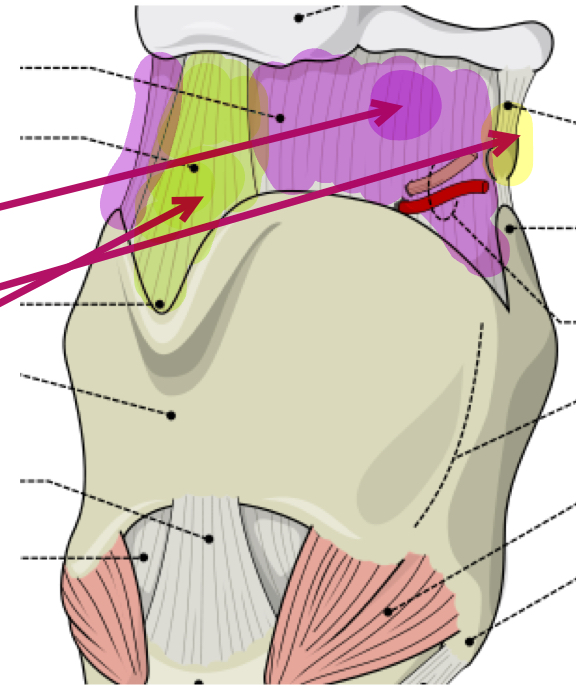

What is the purple membrane?

Thyrohyoid membrane

What is the green ligament?

Middle thyrohyoid ligament

What is the yellow ligament?

Lateral thyrohyoid ligament

What is this muscle?

Lateral cricoarytenoid (LCA) (adduct VF)

What is this muscle?

Transverse arytenoid (adduct VF)

What is this muscle?

Oblique arytenoid (pull apex medially, assist in adducting VF)

What is this muscle?

Posterior cricoarytenoid (PCA) (rocks arytenoid out, abduct VF)